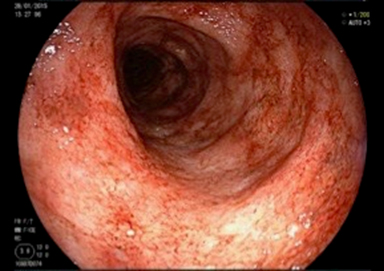

Inflammation aigüe de la muqueuse rectale

Symptomatologie variable : parfois pauci-symptomatique (quelques rectorragies d’allure canalaire) jusqu’à parfois très bruyante (véritable syndrome rectal avec ténesme, épreintes, faux besoins et diarrhée glairo-sanglante, pouvant être associé à des douleurs abdominales)

Etiologies : infectieuses (principalement IST type chlamydiose, gonococcie ; plus rarement Clostridium difficile, amibiase, CMV, tuberculose …), inflammatoires (MICI), traumatiques, ischémiques, iatrogènes (lavement…)